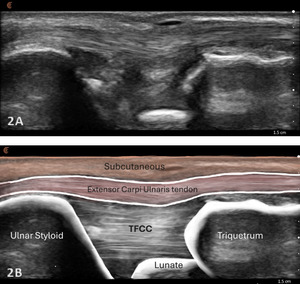

Patient Position: the patient typically sits with the volar forearm on the surface with the dorsal wrist facing superior. The dorsal surface is normally viewed as the structures are more superficial and easier to visualize. The transducer will be placed in the long axis (LAX) and short axis (SAX) to view the TFCC.

Normal Sonographic Appearance

Normal TFCC appears as a thin, continuous, triangular band of homogeneous echogenicity extending from the distal ulna toward the ulnar carpal bones. The margins are smooth and well defined, without fiber disruption or adjacent fluid collection. No abnormal gapping is observed at the ulnocarpal interface, and the surrounding joint recess remains collapsed in the absence of effusion.